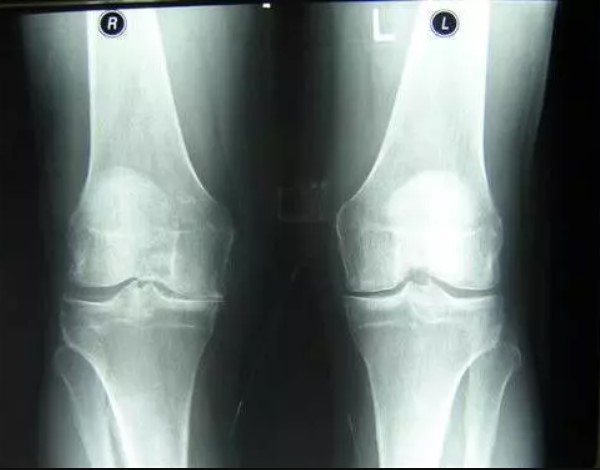

فيما يلي النتائج المرئية للأشخاص الذين شاركوا في الاختبارات باستخدام JointFlex:

علاج مفصل الورك لمريض يبلغ من العمر 44 عامًا. تم الشفاء التام من الآلام الشديدة التي عذبها المريض لمدة عامين:

ترميم مفصل الكوع. مريضة عمرها 31 سنة. مدة العلاج: 12 يوم. استعادة المفصل بالكامل: